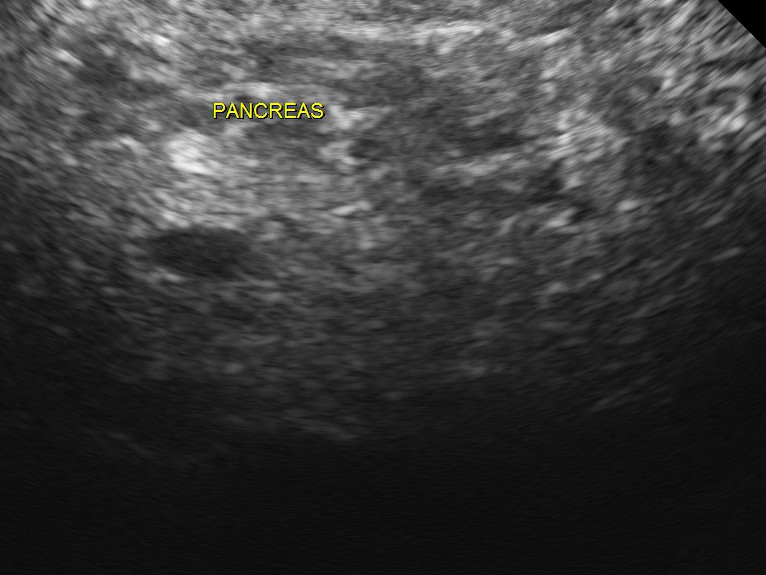

The following pictures were obtained.

An echogenic nodule with vascularity is seen.

3 d reconstruction shows the solid nature and vascularity around and within the nodule.

The appearance of this nodule was suggestive of a metastatic nodule with the increased vascularity around and within.